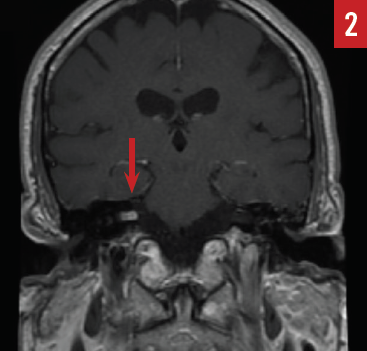

The patient was started on a prednisone 60-mg taper over a 2-week period, which resulted in slight improvement in his hearing. Magnetic resonance (MR) imaging of the internal auditory canals with gadolinium contrast identified an approximately 0.7 × 0.5 × 0.3-cm enhancing mass within the right internal auditory canal suggestive of an AN (Figure 2). After appropriate consultation, the patient elected to undergo stereotactic radiosurgery, and he is being carefully monitored.

Figure 2. MR imaging revealing an enhancing mass in the right internal auditory canal (arrow) consistent with acoustic neuroma (case report 1).